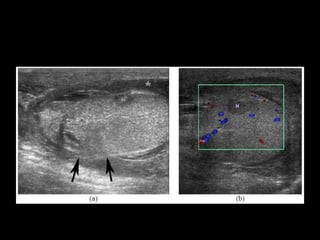

Diagnostico

• USG S-80%, E-85%